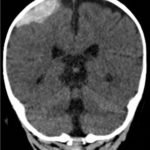

A computed tomography (CT) scan of the head without contrast was obtained out of concern for intracranial pathology due to the patient’s young age and the witnessed focal seizure. The CT showed a 4.2 x 1.2 x 1.5 cm acute extra-axial intracranial right frontoparietal hemorrhage favoring epidural over subdural hemorrhage given its lenticular shape. There was no underlying fracture, herniation or midline shift identified.

Given the concern for non-accidental trauma in this nonmobile child with no history of trauma, pediatric surgery and neurosurgery were consulted and further bloodwork was obtained, revealing elevated partial thromboplastin time (PTT) and a normal prothrombin time (PT). Further work-up led to a diagnosis of severe hemophilia A. He was managed non-operatively with factor VIII infusions to achieve normal factor levels. He remained neurologically stable without further seizure activity during his hospitalization. A skeletal survey showed no fractures. He received levetiracetam for 6 months and had no neurological deficits.